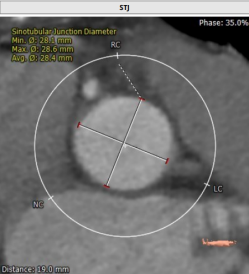

术前CT结果显示,患者主动脉瓣瓣环周长:67.4 mm,平均瓣环直径:21.5mm。左流出道平均直径20.9mm,瓦氏窦最小径31.7mm,窦管结合交界处(STJ)28.4mm,风湿性心脏病,三叶瓣,轻度钙化,瓣叶明显增厚,钙化,左冠开口高度12.2mm,右冠开口高度16.1mm,结合瓦氏窦内径,瓣叶长度及度钙化分布等综合因素考虑,冠脉风险较低,双侧入路血管直径尚可,无明显钙化,最小直径为5.5mm。